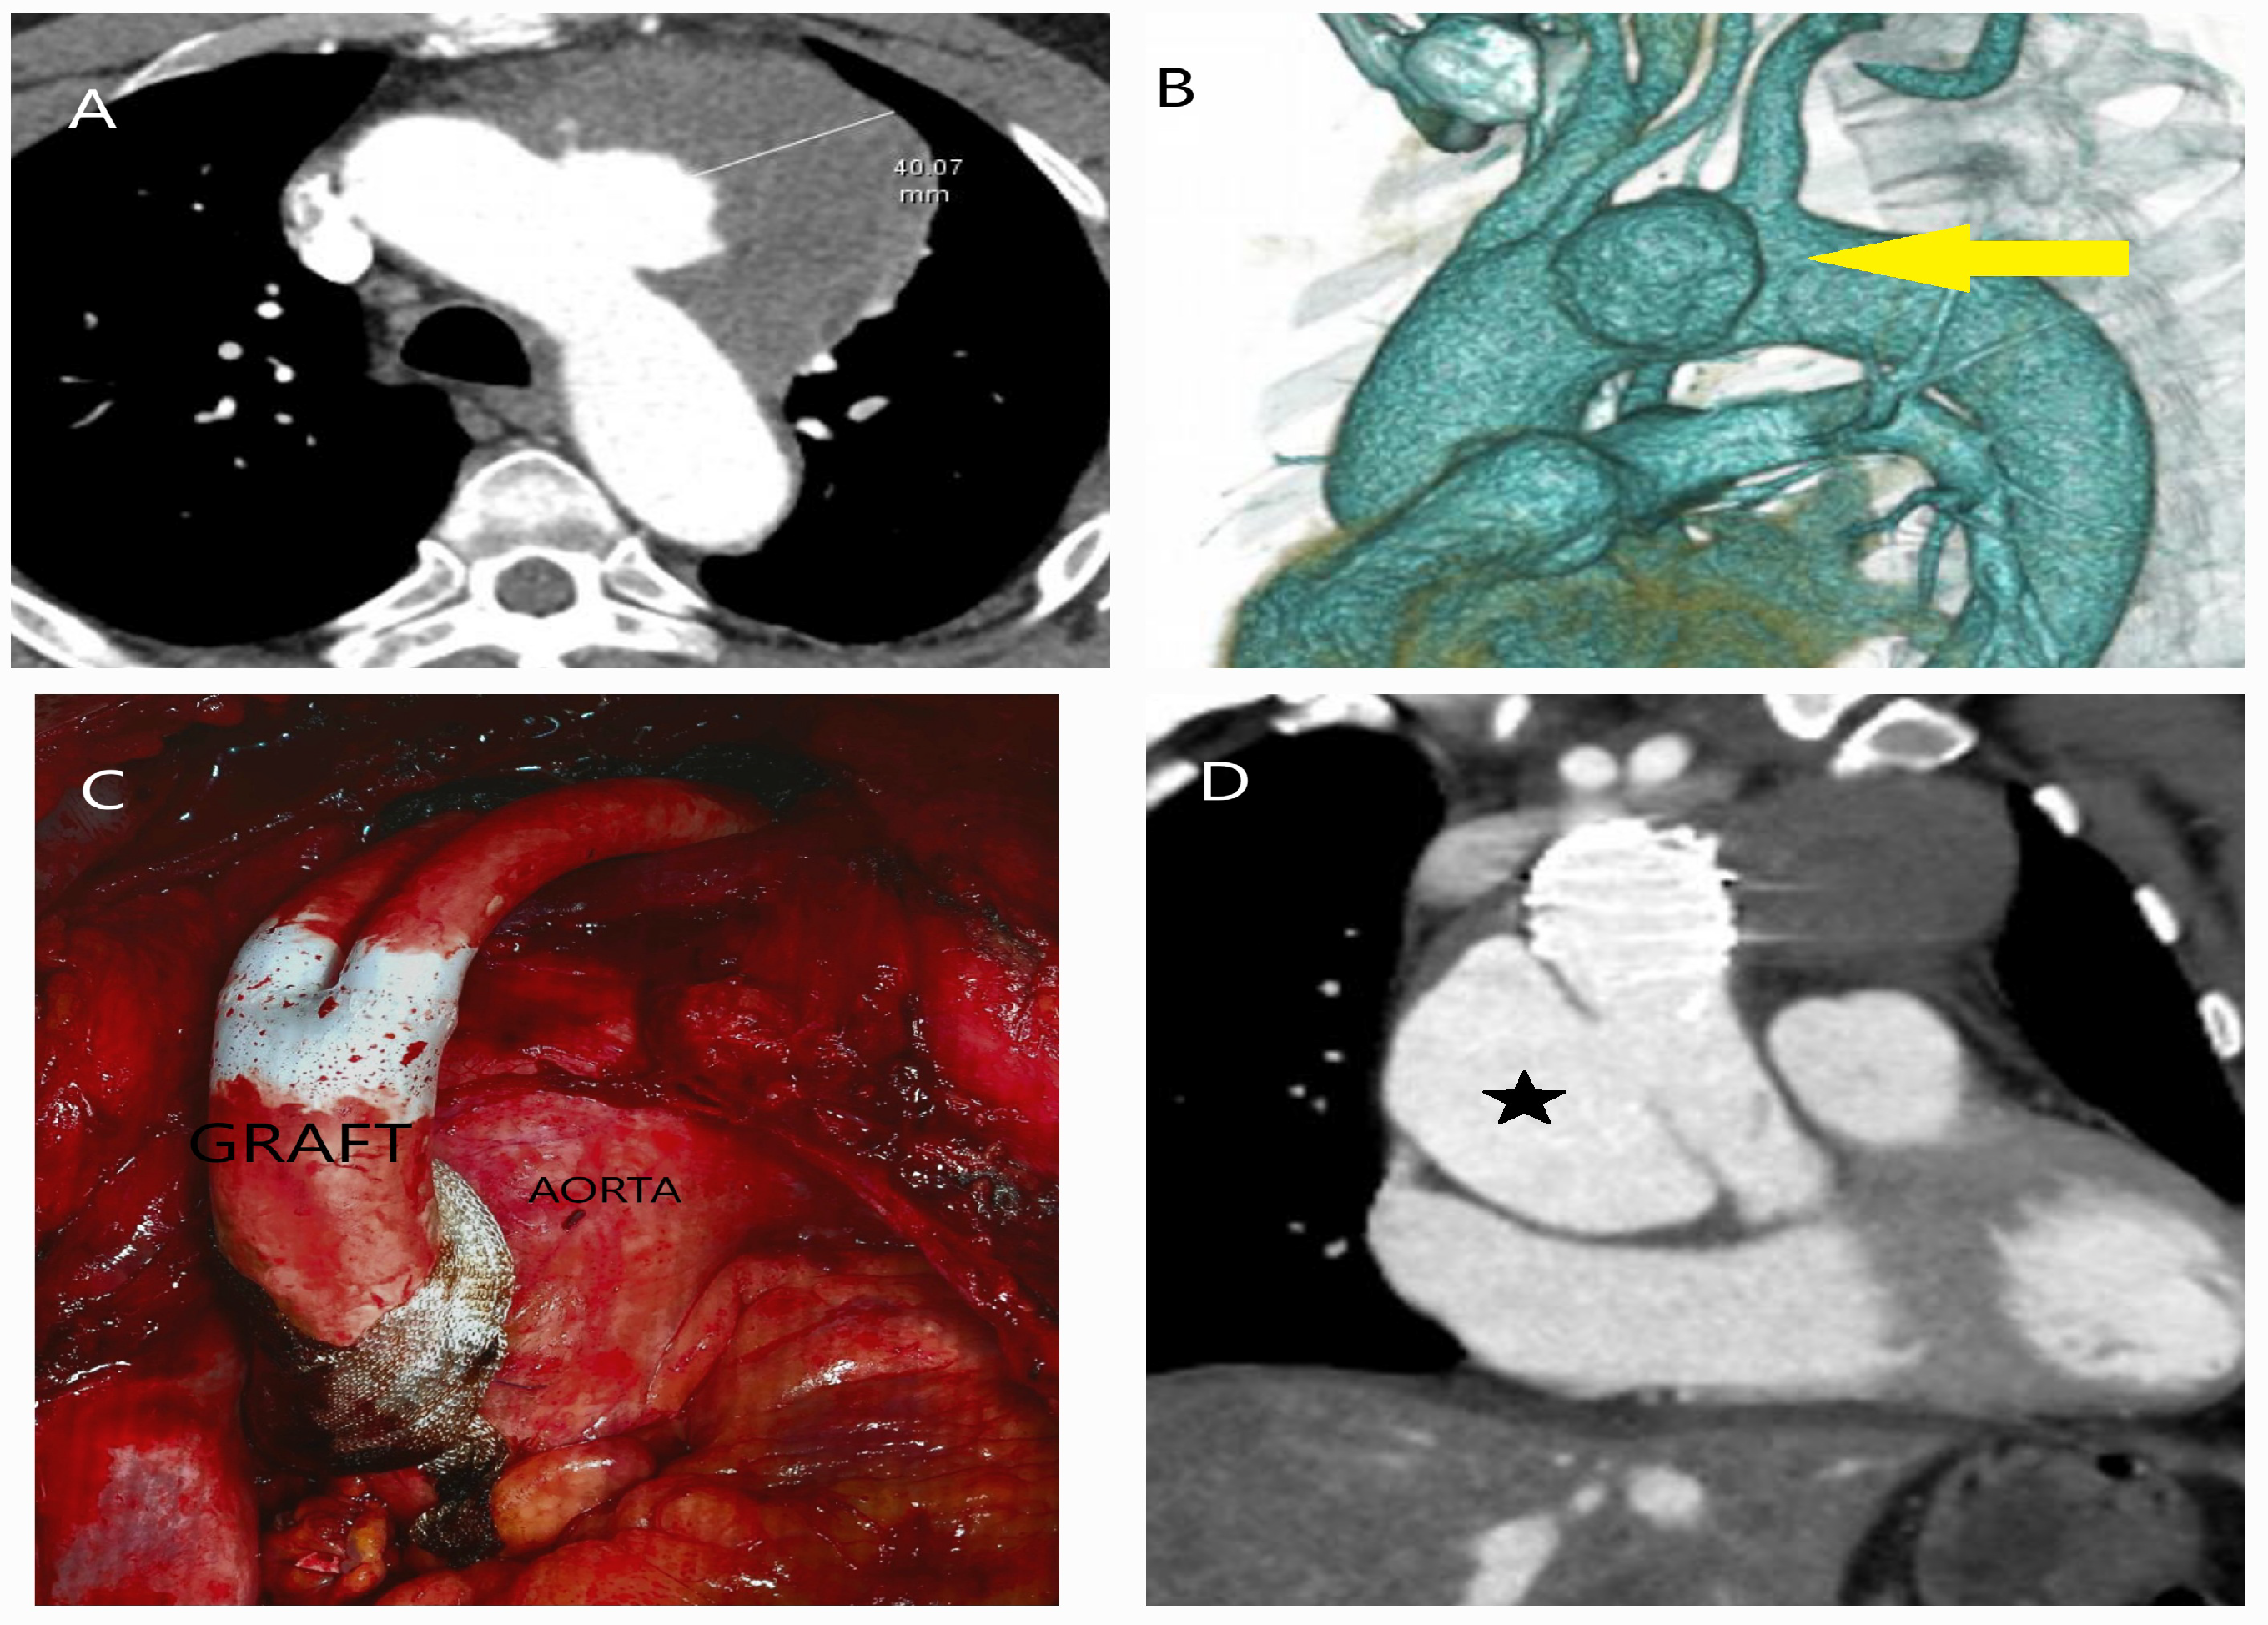

5.2.3. Computed Tomography

- Sathiadoss, P.; Haroon, M.; Wongwaisayawan, S.; Krishna, S.; Sheikh, A.M. Multidetector Computed Tomography in Traumatic and Nontraumatic Aortic Emergencies: Emphasis on Acute Aortic Syndromes. Can. Assoc. Radiol. J. 2020, 71, 322–334. [Google Scholar] [CrossRef] [PubMed]

- Ko, J.P.; Goldstein, J.M.; Latson, L.A., Jr.; Azour, L.; Gozansky, E.K.; Moore, W.; Patel, S.; Hutchinson, B. Chest CT angiography for acute aortic pathologic conditions: Pearls and pitfalls. Radiographics 2021, 41, 399–424. [Google Scholar] [CrossRef] [PubMed]

- Dreisbach, J.G.; Rodrigues, J.C.L.; Roditi, G. Emergency CT misdiagnosis in acute aortic syndrome. Br. J. Radiol. 2021, 94, 20201294. [Google Scholar] [CrossRef]